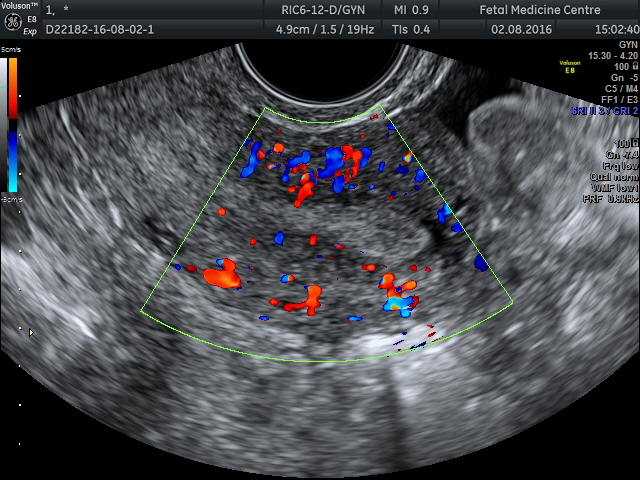

Исследование позволяет получить цветное изображение (врач видит его на экране монитора) и оценить состояние плода, матки, сосудов, плаценты и пуповины.

На специализированном мониторе гинеколог наблюдает цветное изображение, которое позволяет оценить:

- Общий кровоток в маточных сосудах.

- Кровоснабжение через пуповину.

- Состояние плаценты.

- Объем амниотической жидкости.

- Состояние сосудов и артерий матки.

Врач анализирует как приток, так и отток крови. Кровь поступает к органу по крупным сосудам и уходит, унося с собой продукты обмена веществ. Важно, чтобы эти процессы были сбалансированы.